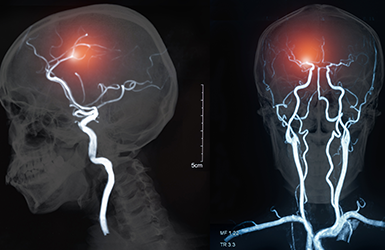

The center boasts specialized medical equipment, namely a state-of-the-art Biplane Interventional & Angiography Suite designed specifically for the prompt diagnosis and treatment of acute stroke, and manufactured by leading medical equipment company Siemens Healthineers. This interventional unit is unique in its sophistication and efficiency. It can evaluate both the brain and blocked blood vessels, allowing doctors to make a diagnosis, administer lifesaving drugs and perform necessary procedures in the same interventional suite, all within the critical first hours of onset. The Comprehensive Stroke Center at LAU Medical Center-Rizk Hospital also includes a dedicated four-bed intensive-care unit and an integrated team of three full-time neurologists, three interventional surgeons, three critical care specialists, and a team of anesthesiologists and neurosurgeons, available to ensure that stroke patients receive the best possible multidisciplinary care 24 hours a day, seven days a week. The center’s location in the LAU Medical Center-Rizk Hospital complex provides patients with quick access to the high-tech resources on site, including a helicopter pad, which can get patients to the help they need when every second counts. Patients also benefit from the hospital’s strong relationships with rehabilitation centers across the country